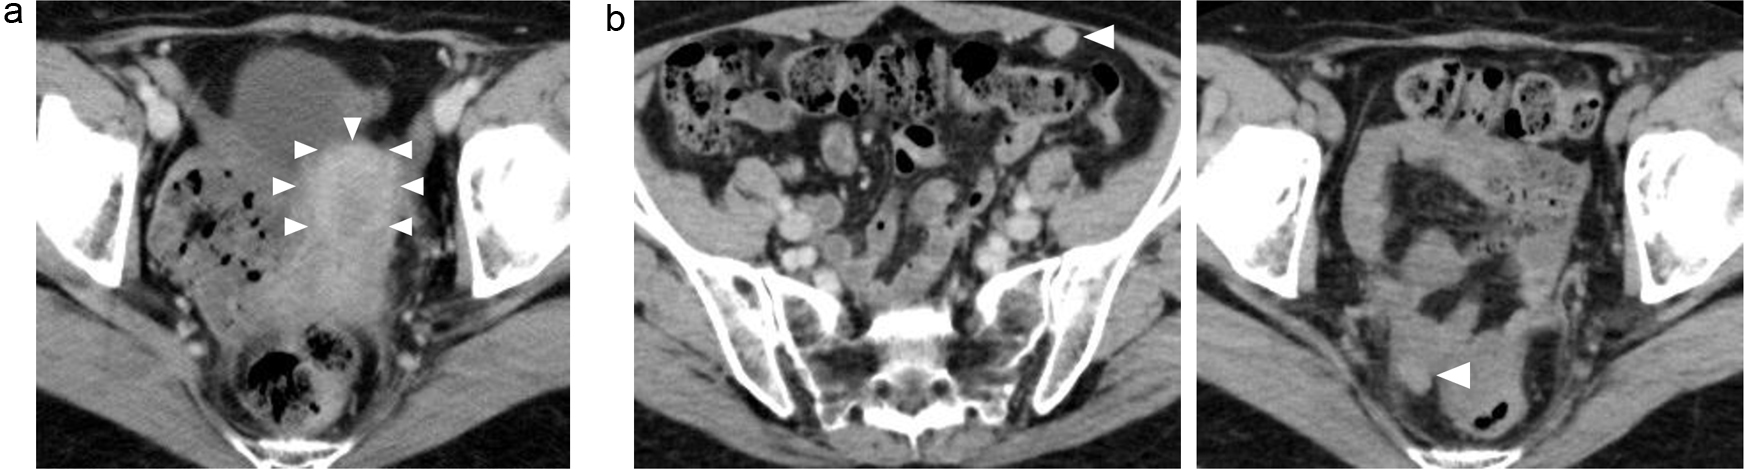

This is a case of a 42-year-old woman with hypothyroidism as comorbidity. The family history revealed that her mother had lung cancer, her paternal aunt had breast cancer, her paternal uncle had pancreatic cancer, and her maternal uncle had prostate cancer and malignant lymphoma. She presented with a left breast mass with pain. A core needle biopsy of breast mass showed invasive ductal carcinoma (IDC). After several examinations, such as computed tomography (CT) and magnetic resonance imaging (MRI), she was diagnosed with 13 × 13 mm breast cancer (cT1N0M0) and underwent breast-conserving surgery with sentinel lymph node biopsy. Pathological analysis showed 12 × 10 mm of IDC with nuclear grade 1, estrogen receptor (ER)-positive, progesterone receptor (PgR)-positive, and human epidermal growth factor receptor 2 (HER2)-negative (pT1N0M0, stage I) (Fig. 1a). She received adjuvant radiotherapy (50 Gy) and endocrine therapy (tamoxifen). At the age of 45 years, the follow-up CT scan revealed a tumor in the uterus (Fig. 2a). She was diagnosed with endometrial cancer and underwent a laparoscopic modified radical hysterectomy with bilateral oophorectomy with pelvic lymph node dissection. Pathological analysis showed localized endometrioid adenocarcinoma, exophytic type, ly0, v0, margin (-), grade 1 (pT1aN0M0) (Fig. 1b). Then she received six cycles of adjuvant chemotherapy, combined with paclitaxel and carboplatin. One year after, the follow-up CT scan revealed multiple intraabdominal masses (Fig. 2b). As peritoneal dissemination from breast or endometrial cancer was suspected, laparoscopic peritoneal dissemination resection was performed. Pathological analysis of peritoneal tumor confirmed the dissemination of endometrioid adenocarcinoma (Fig. 1c). Ten years after breast cancer surgery, mass lesions were noticed in her thoracic cavity on a follow-up CT scan (Fig. 3a). The positron emission tomography-computed tomography (PET-CT) scan showed an accumulation of maximum standardized uptake value (SUVmax) = 2.5 (Fig. 3b). Video-assisted thoracoscopic surgery was performed to identify the primary lesion of this tumor. The pathological analysis revealed the tumor positive for ER, PgR, and GATA binding protein 3 (GATA-3), which led to the diagnosis of metastasis from breast cancer (Fig. 3c).

![]() Click for large image | Figure 2. (a, b) Abdominal CT images revealing the multiple abdominal mass (arrows). CT: computed tomography. |

![]() Click for large image | Figure 3. Examination results for mass in her thoracic cavity by (a) CT, (b) PET-CT (SUVmax = 2.5), and (c) pathological analysis. ER: estrogen receptor; PgR: progesterone receptor; H&E: hematoxylin and eosin stain; CT: computed tomography; PET-CT: positron emission tomography-computed tomography; SUVmax: maximum standardized uptake value. |